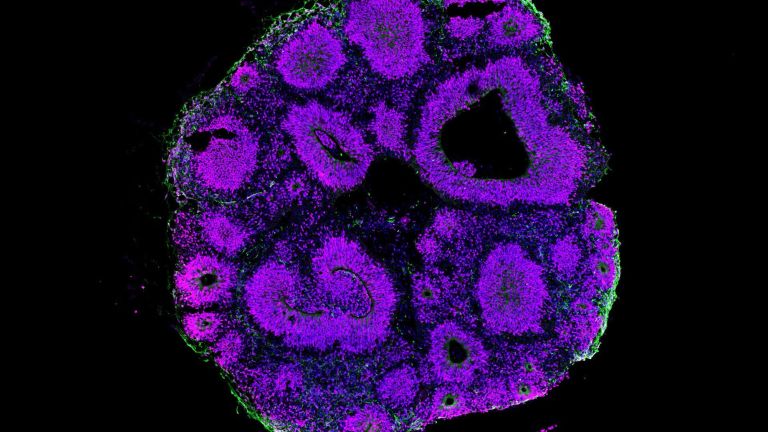

Diese Hirnareale sind durch Nervenfaserbündel mehrfach vernetzt und bilden für semantische und syntaktische Prozesse getrennte Schaltkreise, die sich zu einem Gesamtsprachnetzwerk zusammenfügen. Innerhalb dieses Netzwerks arbeiten diese Schaltkreise, teils parallel, teils seriell, hochdynamisch zusammen. Die Nervenfaserbündel stellen dabei den Informationsaustausch zwischen den einzelnen Hirnarealen sicher. Die Effizienz der Informationsübertragung wird durch eine die Fasern umgebende Isolierschicht, die sogenannte Myelinschicht, gewährleistet. Je besser die Myelinschicht ausgebildet ist, desto schneller die Informationsübertragung. Die heutigen Darstellungsverfahren der Hirnforschung bilden vornehmlich die Stärke der entsprechenden Myelinschicht ab und erlauben somit – zumindest auf der makroskopischen Ebene – einen Einblick in die Verschaltung jener neuroanatomischen Netzwerke, die der Sprachverarbeitung zugrunde liegen.

Im erwachsenen Gehirn können wir drei Faserbündel voneinander unterscheiden. Ein erstes Faserbündel verbindet das für Syntaxverarbeitung zuständige Areal im Stirnlappen, den hinteren Anteil des Broca-Areals (Areal 44), mit dem Schläfenlappen zu einem Schaltkreis, der als Voraussetzung für die Verarbeitung syntaktisch komplexer Sätze gilt. Ein zweites Faserbündel verbindet die für semantische Verarbeitung relevanten Areale im Stirnlappen (Areal 45) und im Schläfenlappen zu einem Schaltkreis, der mit der Verarbeitung von Wort– und Satzbedeutung assoziiert wird. Ein drittes Faserbündel verbindet den prämotorischen Cortex im Stirnlappen mit dem im Schläfenlappen gelegenen auditorischen Cortex und erlaubt das Nachsprechen von Gehörtem. Dieses Netzwerk der linken Hemisphäre garantiert, zusammen mit der für die melodischen Aspekte einer Sprache zuständigen rechten Hemisphäre, die höchst effektive Sprachverarbeitung beim Erwachsenen.

Mit welcher Gehirnausstattung kommt der Säugling auf die Welt? Die Hirnforschung kann hierzu teilweise eine Antwort geben. Bei Neugeborenen sind die sprachrelevanten Hirnareale bereits vorhanden. Interessanterweise findet man aber nur zwei der drei Faserbündel, die bei Erwachsenen vorhanden sind. Jene Faserverbindung, die syntaktische Prozesse unterstützt, ist noch nicht sichtbar, da noch nicht myelinisiert. Sichtbar sind dagegen die anderen zwei Faserverbindungen. Das macht durchaus Sinn. Denn diejenige Verbindung, die auditorischen und prämotorischen Cortex miteinander verbindet, ist funktionell in der frühen Entwicklungsphase bereits hochrelevant, da sie die Lallphase unterstützt, in welcher der Säugling seine Muttersprache hört und versucht, Laute artikulatorisch nachzuahmen. Diejenige Faserverbindung, die die Verarbeitung von semantischen Aspekten unterstützt, bietet die Basisvoraussetzung für das Wortlernen, ein Prozess der ebenfalls früh beginnt.

Erwachsene mit ausgereifter Hirnstruktur haben mit der Verarbeitung von Sätzen, bei denen das Objekt am Anfang des Satzes steht, kein Problem. Sie aktivieren das neuronale Netzwerk, welches für die Verarbeitung von syntaktisch komplexen Sätzen zuständig ist, bestehend aus dem Areal 44 im Broca-Areal und dem hinteren Anteil des Schläfenlappens, zwischen denen eine stark myelinisierte Nervenfaserverbindung besteht. Dieses neuronale Netzwerk ist bei Geburt nicht vorhanden und entwickelt sich langsam. Das zunehmend besser werdende Verstehen von syntaktisch komplexen Sätzen ist bei Kindern zwischen drei und zehn Jahren direkt abhängig von der Reifung dieses neuronalen Netzwerkes. Die Effektivität der Zusammenarbeit der beiden syntaxrelevanten Hirnareale erreicht erst nach dem Alter von acht Jahren einen Status, der dem der Erwachsenen ähnlich ist.

Auf der Ebene der globalen neuronalen Netzwerke jedoch sehen wir interessante Unterschiede zwischen Mensch und nicht-menschlichen Primaten. Die syntaxrelevante Faserverbindung, die beim erwachsenen Menschen zu beobachten ist, ist bei erwachsenen nicht-menschlichen Primaten im Gegensatz zu anderen Faserverbindungen kaum ausgeprägt. Die syntaxrelevante Faserverbindung entwickelt sich sowohl in der Evolution der Menschheit als auch in der Entwicklung des einzelnen Menschen spät. Sie geht Hand in Hand mit der Fähigkeit Syntax zu verarbeiten, die ihrerseits als ein zentrales Element der menschlichen Sprachfähigkeit gilt.